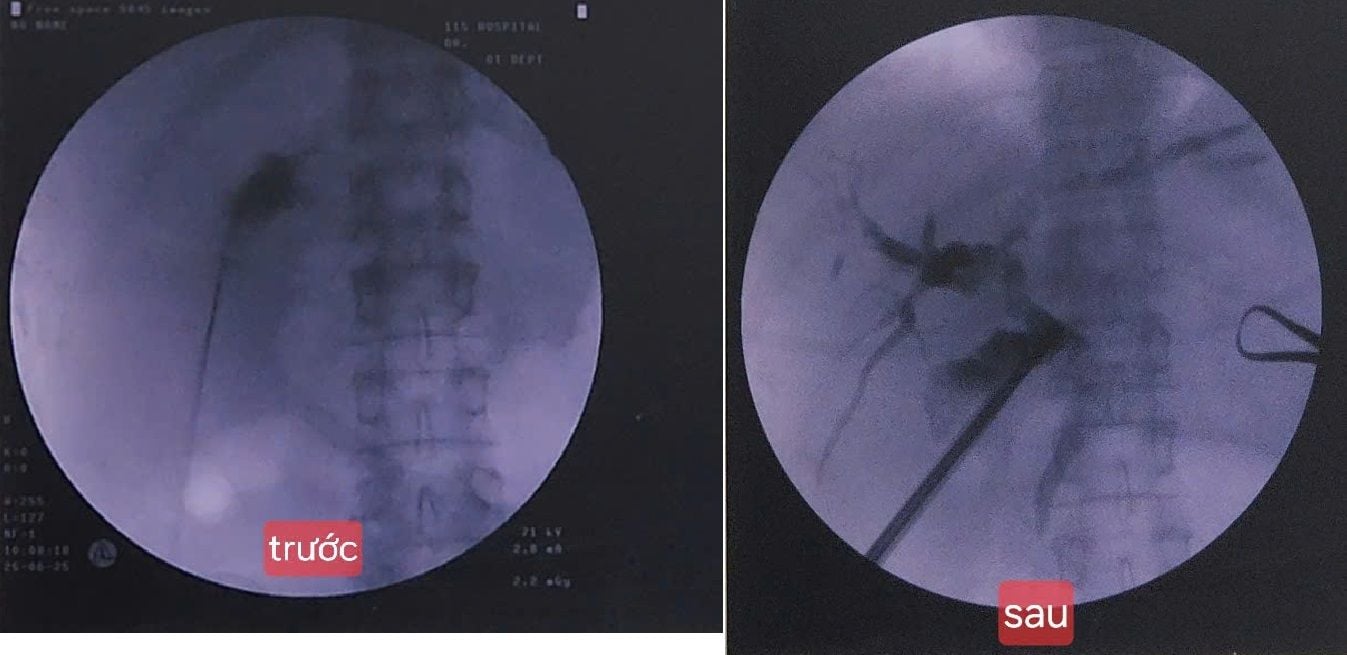

Vừa qua, Bệnh viện Nhân dân 115 (TP.HCM) đã thực hiện thành công ca tán sỏi túi mật xuyên gan qua da đầu tiên tại thành phố – một kỹ thuật hiện đại giúp điều trị sỏi mật hiệu quả mà không cần phẫu thuật cắt túi mật. Đây là tin vui cho những người bệnh bị sỏi túi mật có nguy cơ phẫu thuật cao, nhiều bệnh nền hoặc mong muốn giữ lại túi mật vì lý do sức khỏe lâu dài.

Đây là một kỹ thuật can thiệp tối thiểu, trong đó bác sĩ sử dụng dụng cụ chuyên dụng đi xuyên qua gan, tiếp cận túi mật qua da để lấy hoặc tán sỏi bằng sóng xung kích hoặc các thiết bị tán sỏi khác. Quá trình này thường được hướng dẫn bằng hình ảnh (siêu âm, chụp C-Arm, DSA...) để đảm bảo an toàn và chính xác.

Ca can thiệp được thực hiện trong thời gian ngắn, người bệnh hồi phục tốt và được xuất viện chỉ sau 1 ngày – điều hiếm thấy với các trường hợp tắc mật do sỏi trước đây.